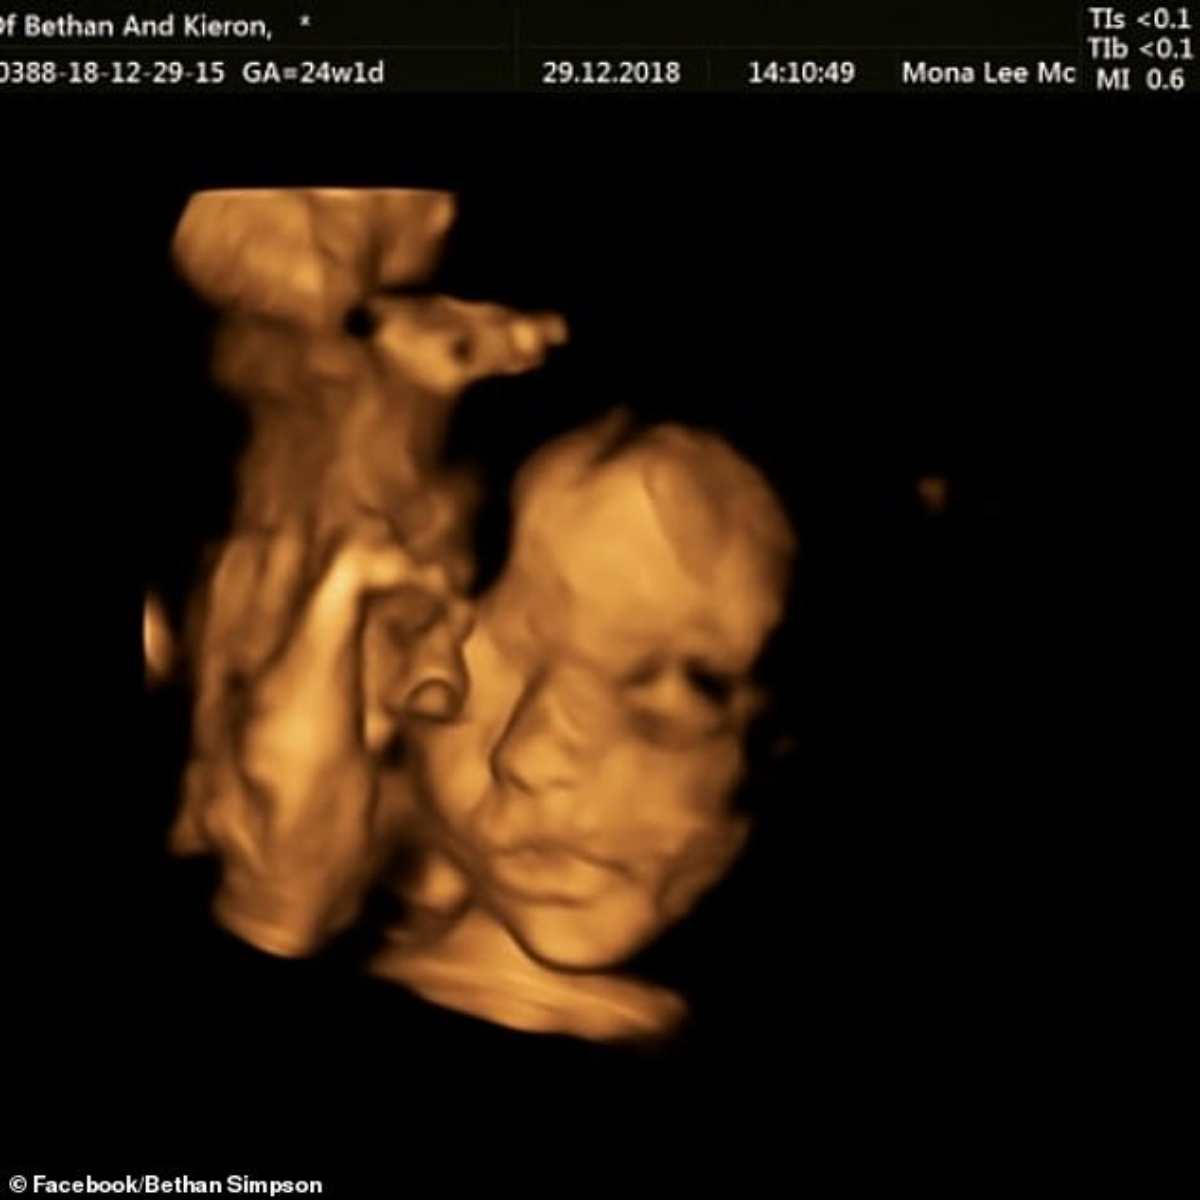

Alla 24° settimana di gravidanza la donna si è sottoposta all’intervento, una delle prime donna nel Regno Unito secondo lei.

I medici hanno rimosso il feto dall’utero, hanno riparato ciò che vi era da riparare e poi l’hanno rimesso dentro al ventre della mamma.